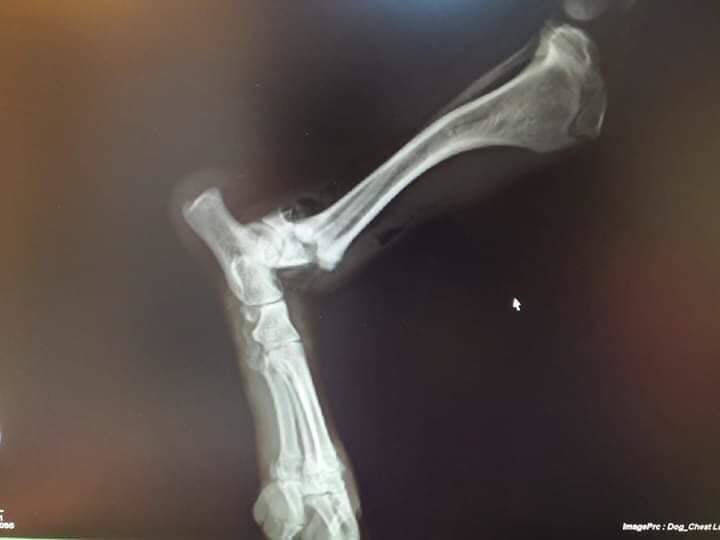

Meet Cleo. She was found in a ditch on the side of the road having been hit by a car. She had 3 broken bones in 2 legs. Her rescuer, Ani, could not afford to pay a vet for the massive veterinary costs that were being quoted by local vets, so Ani asked for our help. We welcomed Cleo into our Homeless Animals Hospital program.

Cleo needed her severly damaged leg to be amputated. She is learning to walk on three legs now. She is recovering at Family Vet in Craiova, and remarkably our Suzy has found her a great home in the UK!